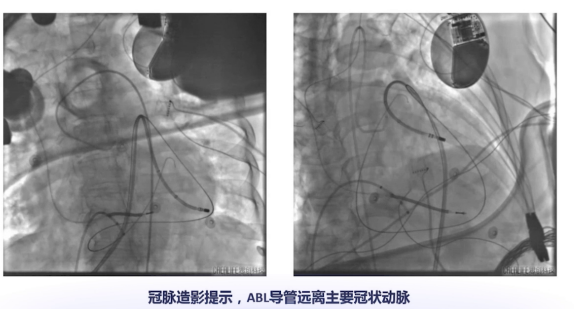

在消融前先进行冠脉造影,确保大头电极所在位置离前降支和回旋支大血管有一定距离,相对安全后开始放电。放电2s即终止室速,随后对关键部位异常电位进行全面消融,以实现瘢痕去通道化或均质化。消融完成后,通过多种频率和形式刺激,均不能诱发室速,表明患者室速成功得到处理。